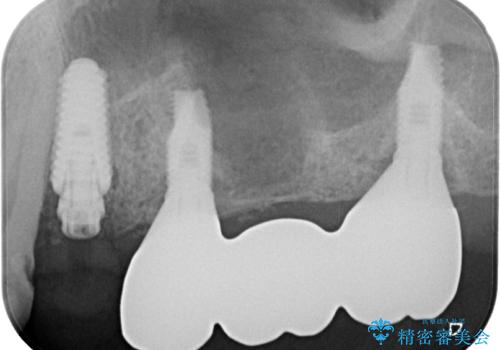

いずれの歯も抜歯が必要な状態であり、抜歯即時埋入によるインプラント治療を行うこととしました。

右上奥歯は骨欠損の範囲が広いため、抜歯即時埋入は可能であっても、即日で仮歯を装着する即時荷重は難しいと判断されたため、手前の歯まで仮歯を装着することとしました。

術後にインプラントの安定値を測定し、十分な値が達成された後、速やかにセラミッククラウンにて補綴治療を行うこととしました。